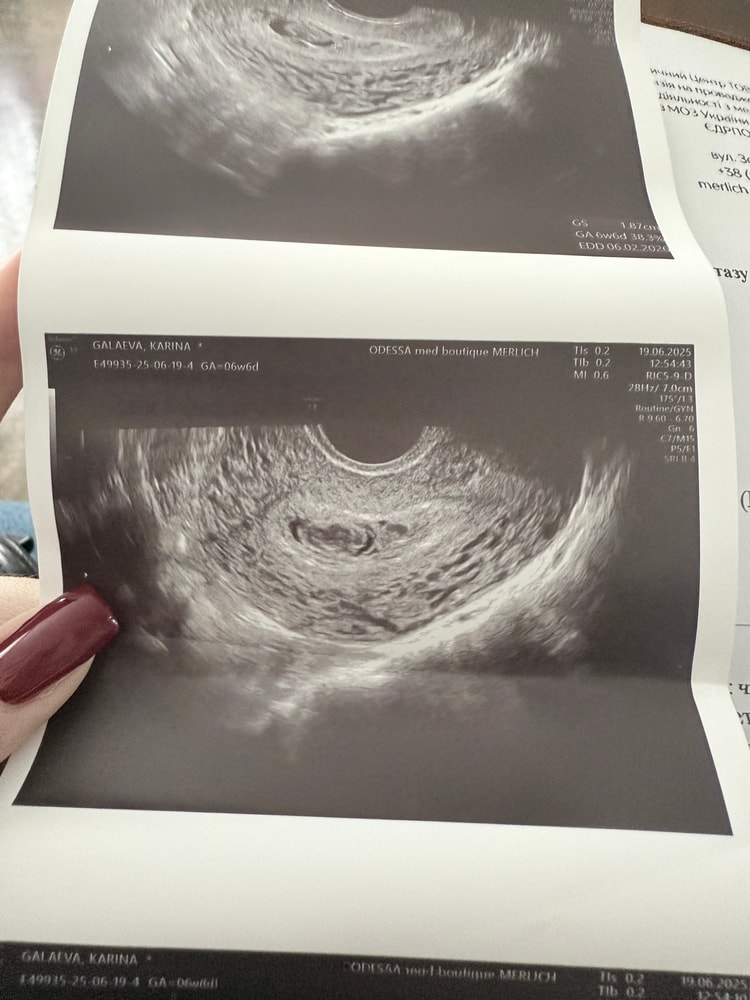

Кира , вот мои результаты с разницей в 3 дня. В итоге у меня малышка сейчас 17 недель. А они чистить собрались в этот день. Изображение Изображение Изображение Изображение